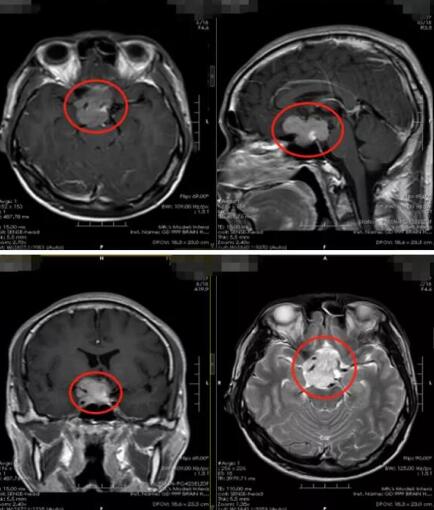

入院后,我院影像检查显示患者鞍区占位。肿瘤压迫视神经,导致患者的视力受损。鲁明分析,“如果不及时处理,瘤体压迫视神经可能会导致失明。”

征得患者及家属同意后,很快,鲁明团队为患者实施了肿瘤切除手术。术后病理结果显示是垂体腺瘤。

“垂体腺瘤是一种比较常见的内分泌腺瘤,属于良性肿瘤。”鲁明耐心地向郑某解释,垂体腺瘤症状多样,主要表现为局部压迫症状和内分泌异常症状。郑某出现的视力减退就属于局部压迫所导致的症状。